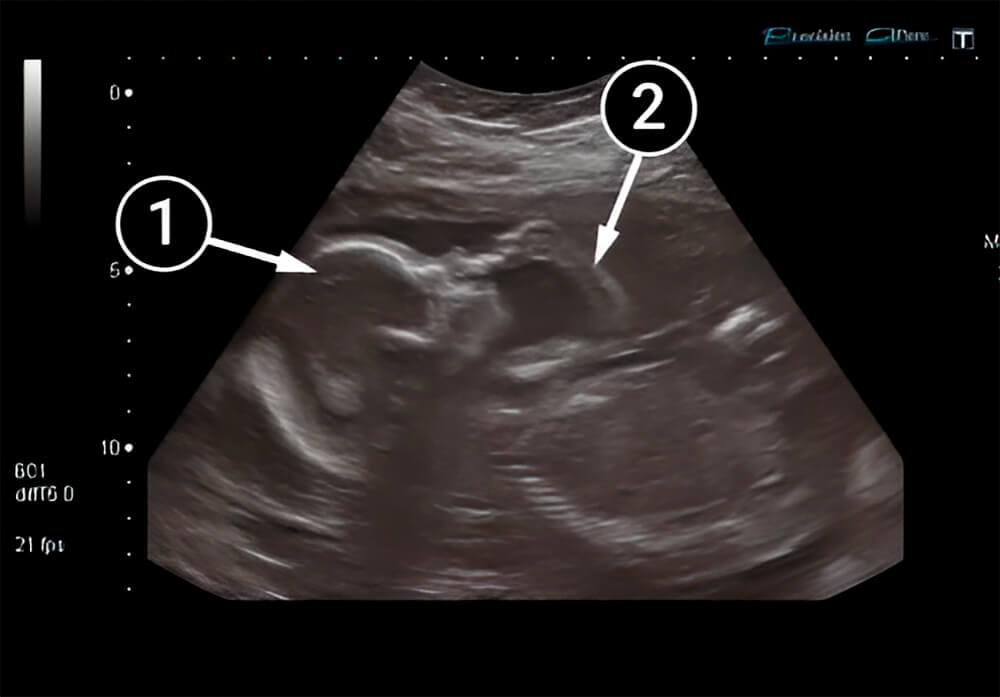

Lo que podemos ver en un ultrasonido

El bebé está boca arriba y se ha llevado un dedo de la mano izquierda a la boca. Su posición indica que está tranquilo y cómodo.

La mano derecha descansa junto al cuerpo y se ven la palma de la mano izquierda y el antebrazo. Los contornos de la cabeza y de la frente también son claros, junto con su pequeña boca y ojos, que se esconden bajo los párpados.